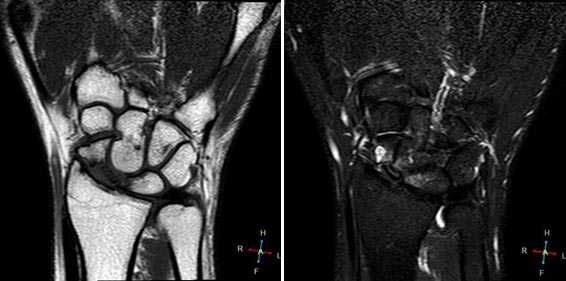

Клинические проявления у пациента: боль и ограничение движений после падения на вытянутую руку 4 месяца назад.

Перелом ладьевидной кости с явлениями асептического некроза проксимального полюса и, связанного с ним, остеоартрита. Ладьевидный перелом обычно происходит из-за падения на вытянутую руку, которое приводит к гиперэкстензии лучезапястного сустава.

Аваскулярный (асептический) некроз нередко сопутствует переломам проксимальной части ладьевидной и переломам полулунной кости, а также неадекватно репонированным и иммобилизированным переломам этих костей. Основная причина - нарушение трофики участка кости при повреждении питающих артерий.

Методом выбора в диагностике и стадировании остеонекроза костей кисти является МРТ.